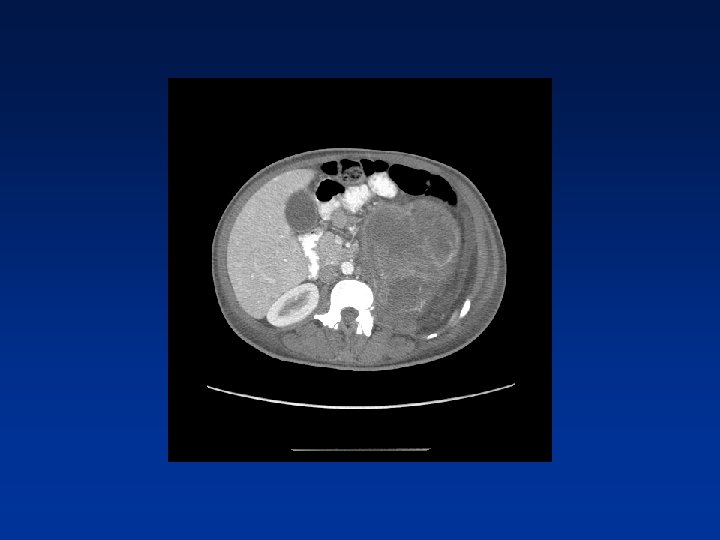

CASE